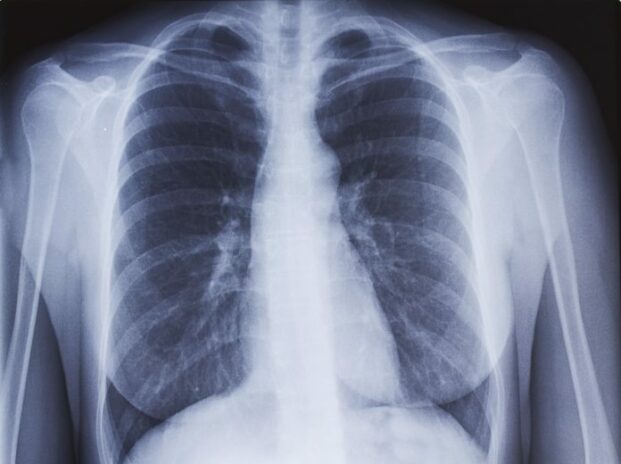

L’examen radiographique permet de visualiser la plupart des organes sans avoir à « ouvrir » le corps ou à introduire de caméra à l’intérieur. Les os, les articulations, les poumons, le système urinaire ou bien encore le système digestif, sont ainsi visibles.

Le saviez-vous ? Le faisceau de rayons X subit différents niveaux d’atténuation :

- Il est important quand il traverse la structure osseuse, d’où la couleur blanche sur la radio.

- Il est intermédiaire lorsqu’il traverse la structure musculaire d’où la couleur grisâtre.

- Il est faible lorsqu’il traverse les poumons (leurs alvéoles sont remplies d’air) d’où la couleur noire sur les clichés radiographiques.